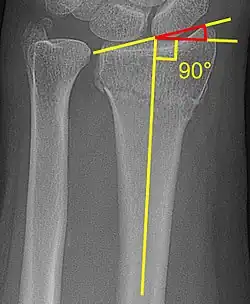

Radial inclination

The radial inclination of a distal radius fracture is shown in red in image at right. The angle is measured between:[5][6]

- A line drawn between the distal ends of the articular surface of the radius on an AP view of the wrist.

- A line that is perpendicular to the diaphysis of the radius.

Radial inclination is normally 21-25°.[7]